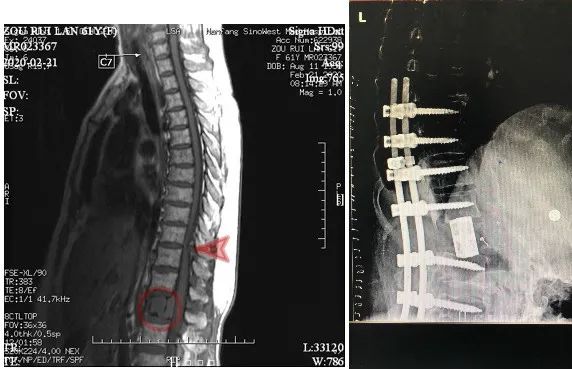

今年2月份,周阿姨突然出现排尿困难,足底发麻的情况,实在难以忍受便在当地医院做了检查,结果提示腰椎肿物。于是慕名来到我院就诊。